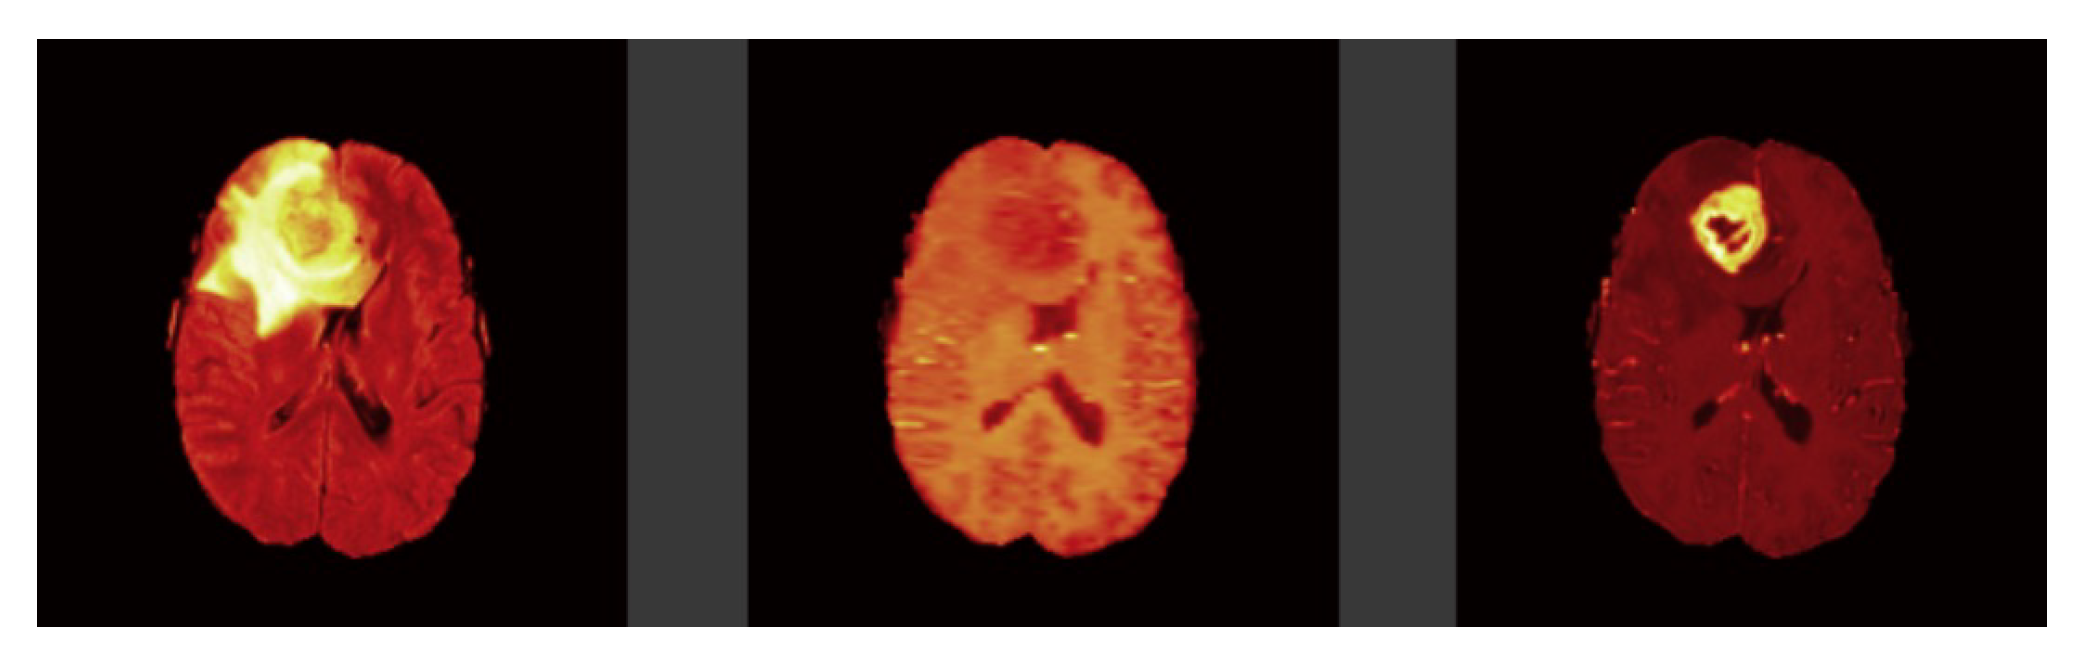

Each model is tested on the test images and the results are compared and are shown in

Table 2. The difference in performance with each model is calculated and shown in the following tables. In

Table 3 the baseline architecture is compared with the four proposed architectures. There has been a considerable performance improvement (the visual results are shown in

Figure 28,

Figure 29,

Figure 30,

Figure 31,

Figure 32 and

Figure 33). From